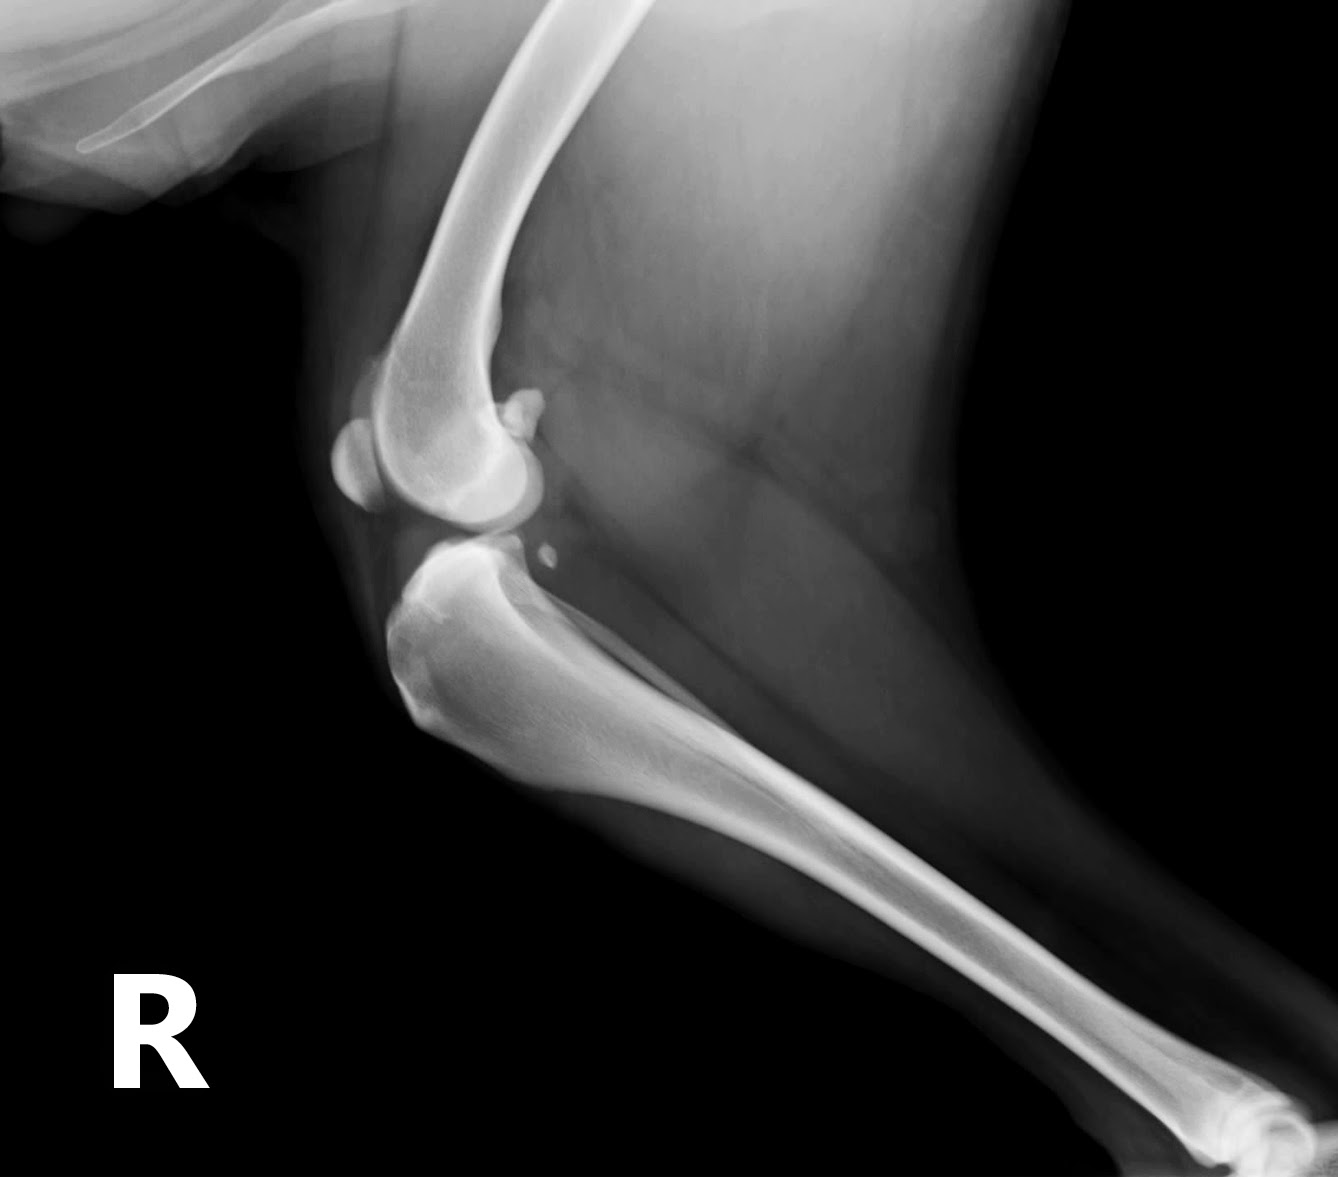

El siguiente paso

fue explorar la rodilla, y se hizo una primera radiografía:

Tenía mucha artrosis

que podría justificar la cojera, aunque en esa imagen no se apreciaba el avance

de la tibia que se produce al romperse el ligamento cruzado.

Al realizar la radiografía a la vez que se

flexiona el tarso, la imagen es mas evidente:

En esta imagen ya se

apreciaba claramente el avance de la tibia, era evidente que el paciente tenía

una rotura del ligamento cruzado anterior, y la solución pasaba por realizar un

avance de la tuberosidad tibial (TTA) para equilibrar tensiones.